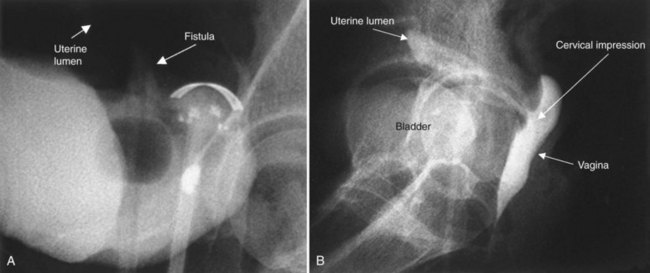

A cystogram and/or voiding cystourethrogram (VCUG) and an upper tract study should be performed in patients being evaluated for a VVF. The cystogram may objectively determine the presence and location of the fistula. Upon filling of the bladder, contrast often begins to opacify the vagina, almost immediately confirming the presence of a VVF. VVF are often best seen in the lateral projection (Fig. 77–7) in which the bladder and vagina are not superimposed. Often, the actual VVF tract may be visible in the lateral projection (Fig. 77–8). However, voiding images may be necessary in some patients with small fistulae, to demonstrate the VVF. The slight increase in intravesical pressure that accompanies micturition is usually adequate to demonstrate even very small fistulae. Importantly, a cystogram that fails to demonstrate a suspected VVF, but lacks voiding images or postvoid images, should be considered nondiagnostic. During voiding, care should be taken to exclude vaginal voiding or reflux of contrast from the introital region cephalad into the vagina, which would produce a falsely positive image. An involuntary bladder contraction can be provoked with rapid filling during cystography, and if the intravesical pressure rises sufficiently, this may also be sufficient to demonstrate a VVF when the filling images of the cystogram failed to demonstrate it. In some instances, a cystogram can also make an assessment of bladder capacity (important in the setting of prior radiotherapy), cystocele, bladder neck competence, and vesicoureteral reflux, any of which may have an impact on operative repair.

Figure 77–7 Cystogram demonstrating a vesicovaginal fistula (VVF). A, Lateral image demonstrates a posthysterectomy VVF. B, Anteroposterior view. The contrast agent is seen opacifying and outlining the vagina superimposed on the bladder.